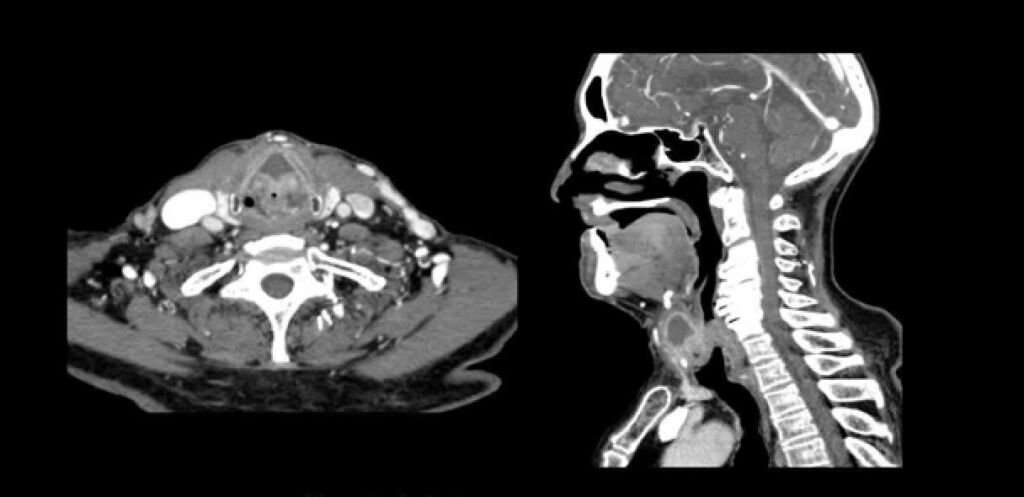

Preparación y procedimiento del examen TAC cervical: lo que debes saber

Un examen de tomografía axial computarizada (TAC) cervical es una herramienta de diagnóstico por imagen que permite a los médicos …

Los beneficios del examen TAC cervical: Descubre por qué es importante para tu salud

El examen TAC cervical es una herramienta médica importante que ayuda en el diagnóstico y manejo de diversas condiciones de …

¿Qué es el Tac Cervical y por qué es importante en Ecuador?

El TAC cervical, o tomografía axial computarizada cervical, es una técnica de imagen médica que utiliza rayos X para crear …